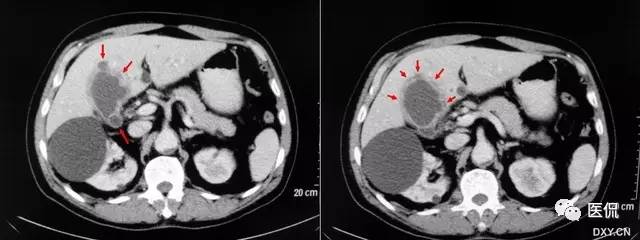

【影像表现】在CT或MRCP及T2W I上增厚的胆囊壁中多发、微小圆点状的高信号囊腔,大小2~7mm,一般为4mm,形似珍珠项圈。

【征象解释】胆囊肌层及上皮增生、肥大,粘膜外翻进入肌层形成罗-阿氏窦。因为罗-阿氏窦内充满胆汁,在MRCP或T2WI增厚的胆囊壁内可呈显著高信号点。

CT及MRI可发现胆囊壁的局限性或弥漫性增厚,以及病变处勒膜层的早期强化和浆膜层的延迟强化,但很难与胆囊炎和胆囊癌相鉴别。罗-阿氏窦内含胆汁,在T2WI上表现为胆囊壁肿块内或增厚的胆囊壁内直径为4~7mm的类圆形高信号灶;在动态增强扫描图像上,表现为增强的肿块内或增厚的胆囊壁内不强化的低或无信号灶。由于动脉期CT或MRI增强比较低的对比度与空间分辨率,较多小的罗-阿氏窦无法显示,动脉期CT或MRI能鉴别最小直径5mm的罗-阿氏窦,而MRCP能鉴别的最小直径是3mm,MRI重T2加权快速自旋回波序列在胆囊腺肌瘤病中的诊断价值已经被研究,因为罗-阿氏窦充满胆汁,在增厚的胆囊壁中可呈显著高信号点。单次激发快速SE序列MRCP很少出现运动伪影和磁敏感性伪影,对于显示罗-阿氏窦,单次激发快速自旋回波序列MRI比动脉期CT或MRI增强扫描及重T2加权快速自旋回波序列更可靠。

珍珠项链征在诊断胆囊腺肌瘤病方面特异性较高,达92%。因此,在诊断胆囊腺肌瘤病和鉴别胆囊腺肌瘤病与胆囊癌中是较为特异性的。MRCP对于显示<3mm的罗-阿氏窦有一定困难。胆囊囊壁内钙化在CT上能帮助诊断胆囊腺肌瘤病,而在MRCP上可能成为一个陷阱。浓胆汁比正常胆汁有更短的T1时间,浓胆汁患者罗-阿氏窦可能无法鉴别。因此珍珠项链征在这些患者中不能被鉴别,特别是用长回波时间的MRCP技术。浓胆汁T1时间短,在T1W I中显示为高信号强度。因此T2W I可能对证明罗-阿氏窦有帮助。因为胆囊壁内脓肿或黄色肉芽肿的存在。黄色肉芽肿性胆囊炎可能显示类似的珍珠项链征。胆囊腺肌瘤病与胆囊癌有时可以共存,员然很少见,但有这样的病例限制了珍珠项链征鉴别胆囊腺肌瘤病与胆囊癌。因此,那些局部胆囊腺肌瘤病的患者特别要密切随访检查,即使在MRCP图像上已明确异示珍珠项链征。